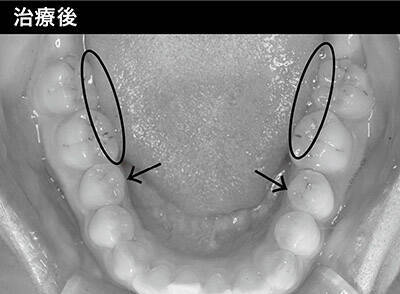

頬の内側、舌に跡が付いていることはありませんか? 今回は跡が付く原因についてお話しします。 歯の外側には頬の粘膜、内側には舌があります。 その2つに跡(歯形)が付く原因はそれぞれ別にあります。 ただどちらも歯に頬や舌を押し付けることによって起こっています。 頬に関しては主な原因は咬みしめです。 普段、唇を閉じた状態(安静時)で上と下のそもそもメガネ跡がつく理由は? メガネ跡がついてしまう理由としては、いくつかの原因が考えられます。 メガネの鼻あて部分は皮膚を圧迫しているため、定期的にメガネを掛け続けている人の場合、色素沈着となってメガネ跡が定着してしまうことがあります。 また、人間の皮膚は年齢を重ねるごとに新陳代謝が低下することから、しみができやすくなります こまめに洗車しているはずなのに、なぜか白い鱗のような染みが残ってしまう場合があります。特に雨上がりの車を放置した後にできやすいようです。その原因は何なのか、どのように対策すればいいのか紹介します。

その2つに歯形の跡が付く事があり、その原因はそれぞれ別にあります。 ただどちらも共通して言えるのは、歯に頬や舌を押し付けることによって起こっています。 ~頬に関しては主な原因は強い咬みしめです。 ~ 普段、人は唇を閉じた状態(安静時)で上と下の歯は接触していないのが正常です。 等が起こると人は咬みしめを起こしているがあります。 これを 指輪跡関する内容や跡を消す方法を紹介してきました。 様々なものがありますが、結論としては、 『指輪をしている以上、指輪跡がつくのは仕方のないこと』 だと言えます。 日頃から、指輪の手入れや付ける時間を考えたりなど、 『指輪跡を付けない努力』子供の頃は気にならなかった靴下を脱いだ時の跡。 大人になるにつれてだんだんと靴下の跡が消えにくくなったと思いませんか。 実はこれ、足のむくみと大きく関係しているのです。 足のむくみの原因と対策をまとめまてみました。 スポ・・・

小さい顎に憧れる 舌に歯の跡がつく 不調がある人に注意して欲しいこ 年7月5日 エキサイトニュース 8 9

頬圧痕とは 田端の歯医者なら しおばら歯科医院 痛くない 怖くない歯医者です

舌ストレス症候群の治療 改善方法 あごが小さい 舌に歯の跡がつく原因は 咀嚼不足 めまいや滑舌の悪さ 舌がんリスクなどを招く 特選街web